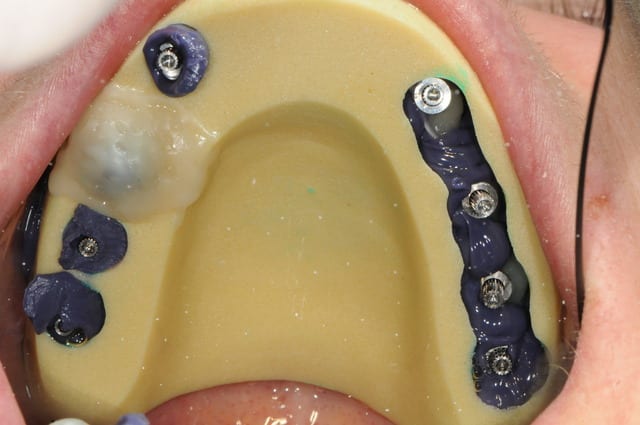

23/06/2010 à 01h44

l'heure des comptes va bientôt sonner...

je débute la prothèse définitive, ai je raison de m'y prendre si tôt ?

vos avis ...

nous ne sommes qu'à deux mois et demi.

pour ce qui est du PE, je me suis trompé grave sur le nombre de transfert d'empreinte pick up à commander, je l'ai donc fait avec un pop-in

Dsc 7721 ynef61 - Eugenol

Dsc 7729 pcarw2 - Eugenol

Dsc 7724 ttveeb - Eugenol

Dsc 7726 smacig - Eugenol

Dsc 7728 dhm8q4 - Eugenol